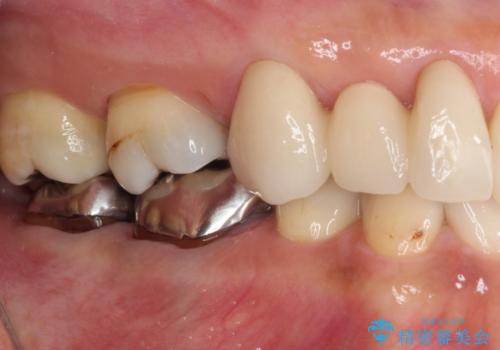

- 残存している乳歯や欠損部の隙間を気にして来院された患者様です。

上顎は左右ともに小臼歯が欠損しており、右側は乳前歯が残っている状態でした。

ブリッジによる補綴治療にて、欠損や隙間を補完することとしましたが、神経を取り除いたり、審美的に不自然になることを避けるため、部分矯正を併用することとしました。

乳歯は事前に抜歯することとしました。